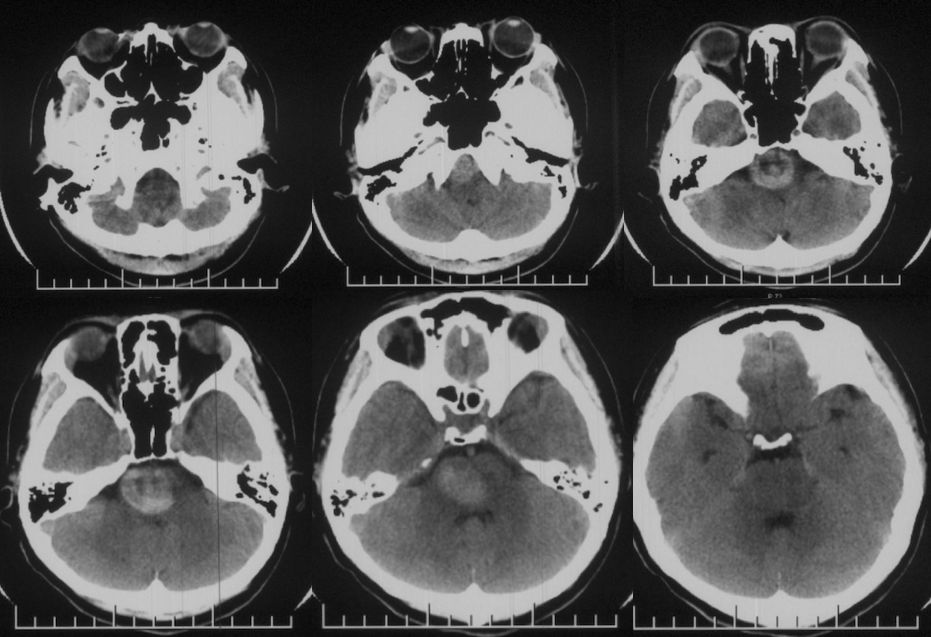

当地医院头CT:右侧脑干占位(2019-09-06)(图1)。

图1

当地医院MRI:基底动脉中上段夹层动脉瘤(2019-09-16)(图4)。

图4

2、头部核磁共振显示:脑干占位性病变,边界较清晰,较大层面大小约35 mmx25 mm。MRA显示:基底动脉夹层动脉瘤。DSA显示,基底动脉巨大夹层动脉瘤,最大长径为:10.8 mm,最大短径为3.2 mm。根据患者症状及影像学诊断,基底动脉巨大夹层动脉瘤进行性增大压迫脑干,不排除脑干水肿可能,亟待手术治疗。